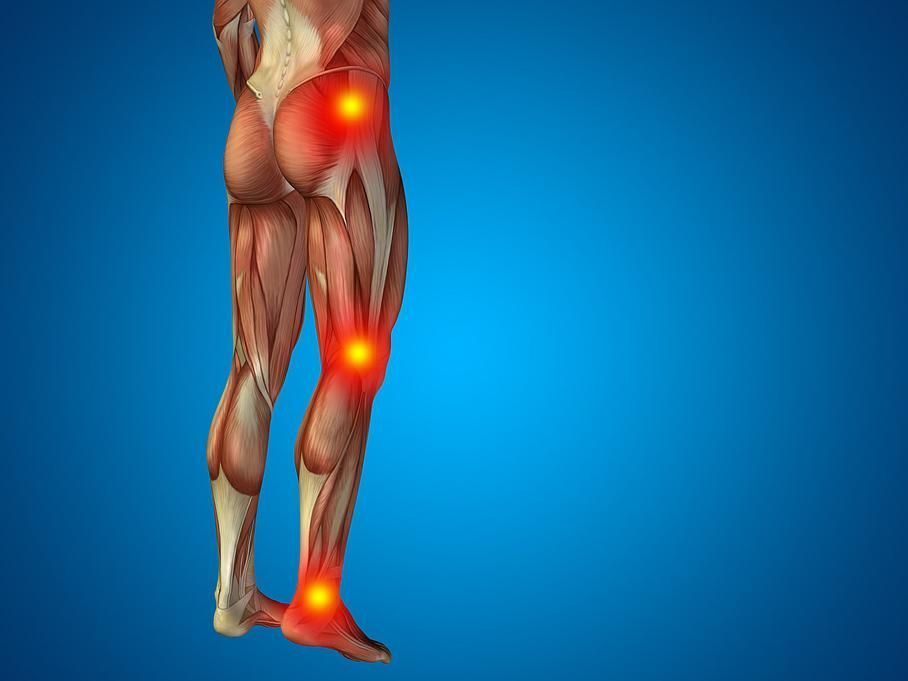

MEMBRES INFERIEURS

Conflit antérieur de la hanche:

Lors du conflit, une douleur et une limitation de la mobilité de la hanche surviennent. Ce contact répété va provoquer des lésions du bourrelet et du cartilage. L’évolution se manifeste par une dégradation de l’articulation et une majoration de la gêne.

Arthrose de la hanche, ou coxarthrose:

L’évolution d’une arthrose de la hanche se fait par usure du cartilage et apparition de douleurs qui deviennent handicapantes pour la personne. Une fois le cartilage abîmé, il n’existe pas de solution médicale pour le reconstituer.

Pathologies du genou:

Les pathologies de la cheville:

Les entorses et instabilités:

Les tendinites et rupture du tendon d’Achille:

Les douleurs au tendon d’Achille, c’est-à-dire sur la partie postérieure de la cheville, sont une maladie fréquente et nécessitent une prise en charge médicale, souvent de longue durée.

Les douleurs au talon: